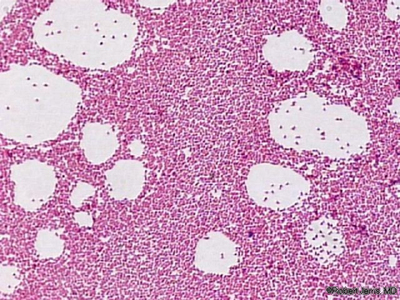

Pemeriksaan biopsi hati dijumpai gambaran kejadian inflamasi difus yang menyerupai hepatitis dengan agregasi sel-sel mononuclear, kadang-kadang juga terlihat berbentuk granulomatus. Juga telah dilaporkan bentuk abses hepar yang piogenik.